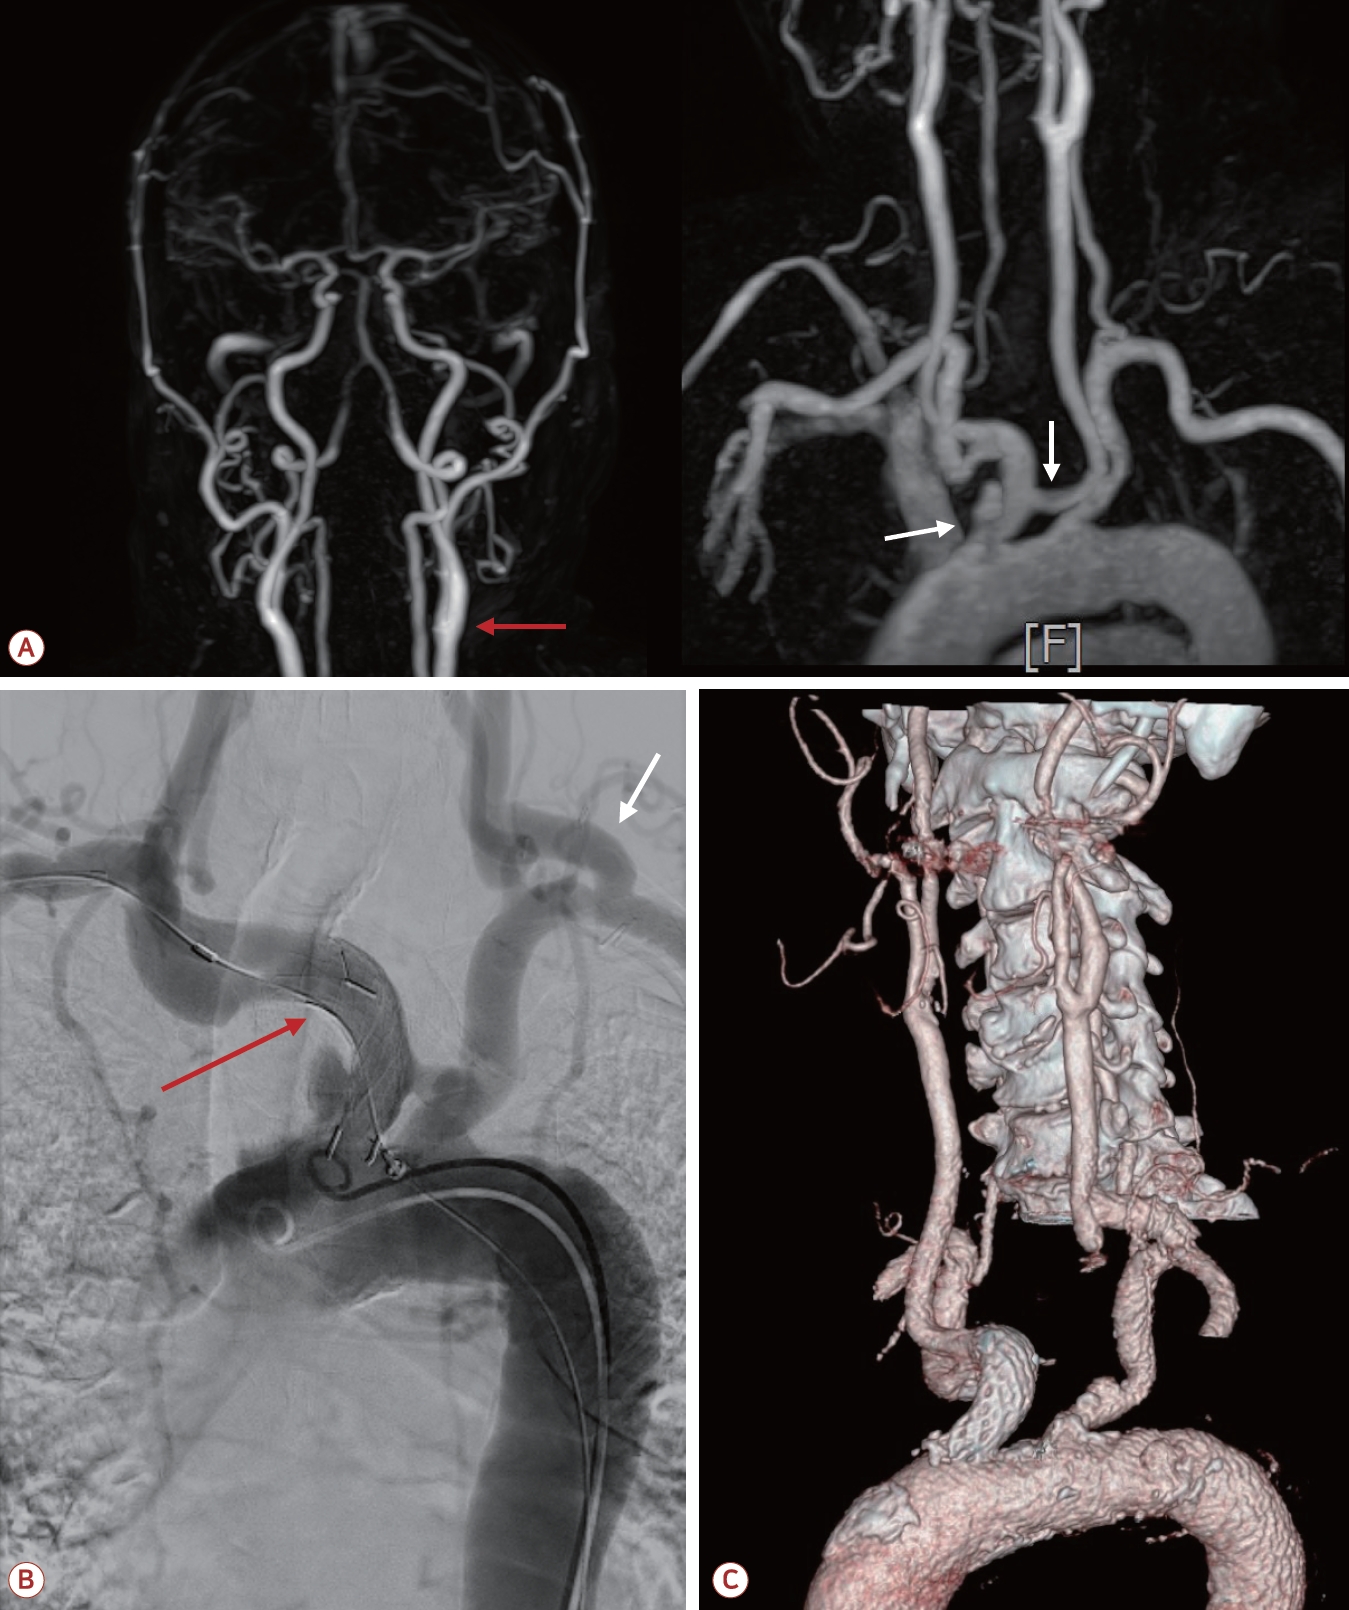

73세 남자가 최근 3개월간 반복적인 허혈뇌졸중으로 내원하였다. 환자는 고혈압, 당뇨, 안정협심증의 기저 질환을 가지고 있었다. 초기 뇌자기공명영상(magnetic resonance [MR] imaging)에서 좌측 대뇌반구와 우측 소뇌에 다발성 허혈 병변이 관찰되었으며(Fig. 1-A) 혈관 검사에서는 좌측 내경동맥근위부(internal carotid artery, ICA)에 76.7%의 협착(NASCET 기준)이 확인되었고 동시에 보바인형 대동맥궁(bovine arch, 공통 기시형 변이)이 관찰되었다(Fig. 1-B). 이에 따라 증상성 중증도 이상의 ICA 협착으로 판단하여 좌측 CEA와 이중 항혈소판 요법이 시행되었다. 그러나 시술 2개월 후에 우측 후 대뇌동맥(posterior cerebral artery, PCA)과 우측 중대뇌동맥(middle cerebral artery, MCA) 영역에 재발성 뇌경색이 발생하였고(Fig. 2-A) 한 달 후에는 좌측 MCA와 PCA 영역에 새로운 뇌경색이 재발하였다(Fig. 2-B). 기존에 진행되었던 두개경유도플러 검사에서 심방중격 결손이나 미세색전 신호를 시사하는 소견은 확인되지 않았고 흉부경유심초음파에서 좌심실 박출률은 정상 범위었으며 3일의 홀터 모니터링에서도 심방세동은 관찰되지 않아 심장성 색전은 배제하였다. 반복되는 색전성 병변의 원인을 찾기 위하여 식도유심초음파(transesophageal echocardiography, TEE)가 진행되었으며 대동맥궁 대만부(greater curvature)에 위치한 7 mm 크기의 궤양성(ulcerated), 유동성(mobile)의 고위험 죽경화판(high-risk aortic arch plaque)이 관찰되었다(Fig. 2-C). 추가적인 머리 혈관조영에서는 기존에 확인되었던 좌측 경동맥의 중증도 협착은 호전 상태를 보였으며 보바인형 대동맥궁 및 팔머리동맥에 동맥류성 확장(aneurysmal dilatation)을 확인할 수 있었다(Fig. 3-A). 이에 신경과, 순환기내과, 영상의학과, 심장혈관흉부외과가 포함된 다학제 협의를 통해 단계적 하이브리드 치료가 결정되었다. 첫 번째 단계로 부분 디브랜칭 수술(좌쇄골하-좌총경동맥우회술[partial debranching surgery, left subclavian-left common carotid artery bypass])이 시행되었다. 수술 한 달 후에 팔머리동맥에 스텐트이식편(endovascular brachiocephalic stent-graft)을 삽입하여 팔머리동맥류의 병적 분절을 제거하였다(Fig. 3-B, C). 스텐트 시술 이후 약 1년 6개월이 지난 현재까지도 환자는 지속적으로 이중항혈소판 요법을 유지하면서 추가적인 허혈 사건 없이 안정적으로 추적 관찰 중이다.

하이브리드 접근법은 수술적 우회술과 혈관 내 치료를 결합하여 각각의 장점을 극대화하는 방식이다. 본 증례에서는 1단계로 부분 좌쇄골하-좌총경동맥우회술(partial debranching surgery)을 통해 뇌혈류를 확보하였고 수술 한 달 후 2단계로 팔머리동맥에 스텐트이식편을 삽입하여 동맥류와 죽경화판을 제거하였다. 이러한 단계적 치료를 통해 수술이나 단독 혈관 내 치료만으로는 얻기 어려운 효과를 얻을 수 있었다.